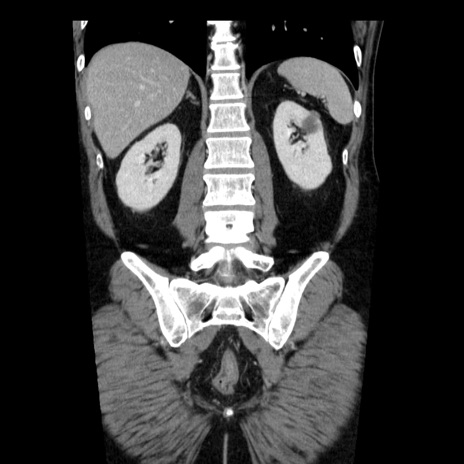

症例29(冠状断像)

【症例】40歳代男性

【現病歴】2日前から胃痛あり。徐々に周期的な激痛に変化した。本日になっても激痛があるため受診。

【身体所見】意識清明、BT 38-39℃台あり、腹部:膨満、やや硬、右下腹部に圧痛あり。

【データ】WBC 8500、CRP 23.26